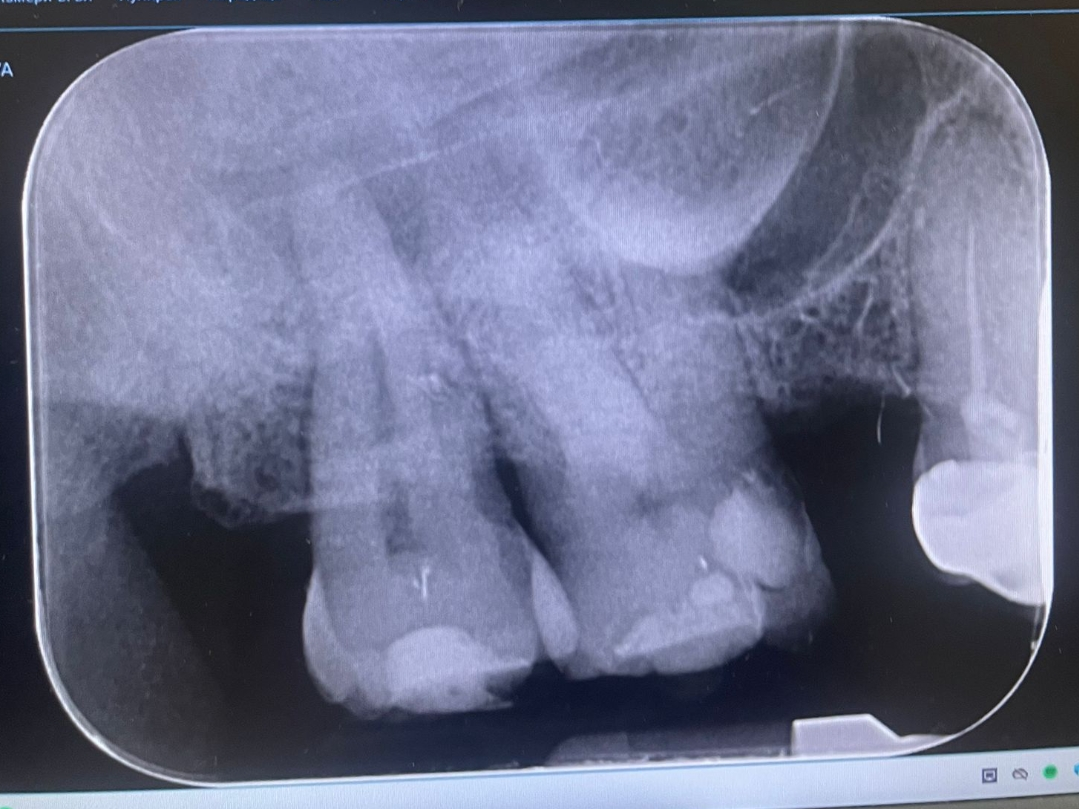

Здравейте искам второ мнение. На снимката предния зъб от дясно с пломбата според зъболекаря ми има лека сянка и е за вадене на нерви. Какво да мисля първоначално каза че няма проблем и в последствие друго.

Правих снимка и преди месец пак каза че няма проблем.

Сега избелвах зъбите първо с шини,после едно кабинетно избелване. Сега ако извади нервите на предния зъб няма ли да това да окаже влияние на вече избелените зъби.

Първоначално като видя снимката каза че няма проблем, впоследствие няколко дни по късно каза че има сянка от 1мм и сигурно е тръгнала гангрена, което мисля че е само за да вземе още пари. Пломбата е за смяна да,но изчакваме да мине малко време защото избелвах. Трябва да се стабилизира цвета за да сменим пломбата да прецени цвета.

Умъртвяванено на зъба според мен е доста крайно при положение че един път е казала едно,а после друго, нямам и болки. Досега за месец първо избелвах с шини и после едно кабинетно избелване като съм дала 900 лв и чистене на зъбен камък в това число.